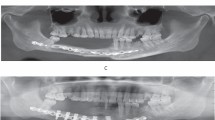

The model’s ability to quantify changes allows for more sensitive detection of alterations compared to human observers. As illustrated in Fig. 2, two input images were captured with a 3-h interval (A: 2 h post-initial salvage procedure, B: 5 h post-initial salvage procedure). While the second image shows a slight increase in the congestive margin compared to the first, the difference was subtle enough that clinicians deemed the flaps similar and deferred further salvage procedures. However, the model indicated a significant change, estimating a 1.3% probability of vascular compromise in the flap in the first image, which increased nearly tenfold to 13% in the second image. Subsequently, this patient underwent a second salvage procedure 15 h after the initial one. Despite these interventions, the vascular compromise remained unresolved, ultimately necessitating flap removal.

Input images from a 58-year-old male patient who underwent glossectomy and pharyngectomy for oropharyngeal cancer, with the defect repaired using an anterolateral thigh flap. The patient exhibited congestive symptoms following the initial surgery, prompting vein re-anastomosis after 11 h. The image on the left shows the model’s analysis 2 h after re-anastomosis, while the image on the right represents the analysis 5 h after re-anastomosis.